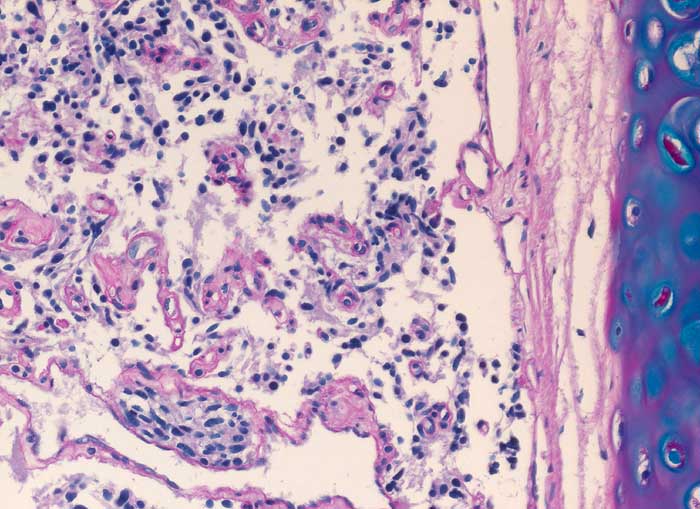

Spindelzellige Tumorzellnester bilden kleine von schmalen Bindegewebssepten mit Kapillaren umgebene Zellnester. Der Tumor infiltriert die Submukosa.

Da es sich nur um eine sehr kleine Biopsie handelt, kann ein atypisches Karzinoid (Nekrosen, Mitosen) nicht ausgeschlossen werden.